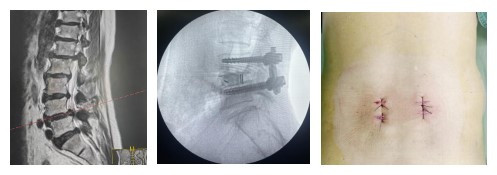

2025年3月26日,急诊科送来一位因严重摔伤导致全身多处疼痛、颈部活动障碍的患者韦先生。影像学检查结果令人心惊:枢椎椎体及附件、齿状突骨折,伴随寰枢关节半脱位。寰枢椎(C1-C2)位于颅颈交界处,毗邻脑干、脊髓和椎动脉,是控制呼吸、心跳的神经中枢所在。此处的骨折,尤其是不稳定型齿状突骨折,如同在人体最重要的“承重柱”顶端安放了不稳定的“爆破点”,随时可能因微小的移位导致高位截瘫、呼吸心跳骤停,历来是脊柱外科中风险最高、最令医生敬畏的挑战之一。

经过严谨的术前讨论和充分的准备,2025年4月1日,他为患者施行了“颈后路枢椎骨折切开复位内固定术”。手术台上,他目光如炬,手法稳如磐石,在放大镜与神经监测仪的辅助下,小心翼翼地避开重要的神经与血管,成功将移位的骨折块精准复位并牢固固定。当监测仪上显示患者神经功能一切正常时,手术室内所有人都松了一口气。术后第三天,患者便在支具保护下开始下床活动,并于4月14日康复出院,重新挺直了脊梁。